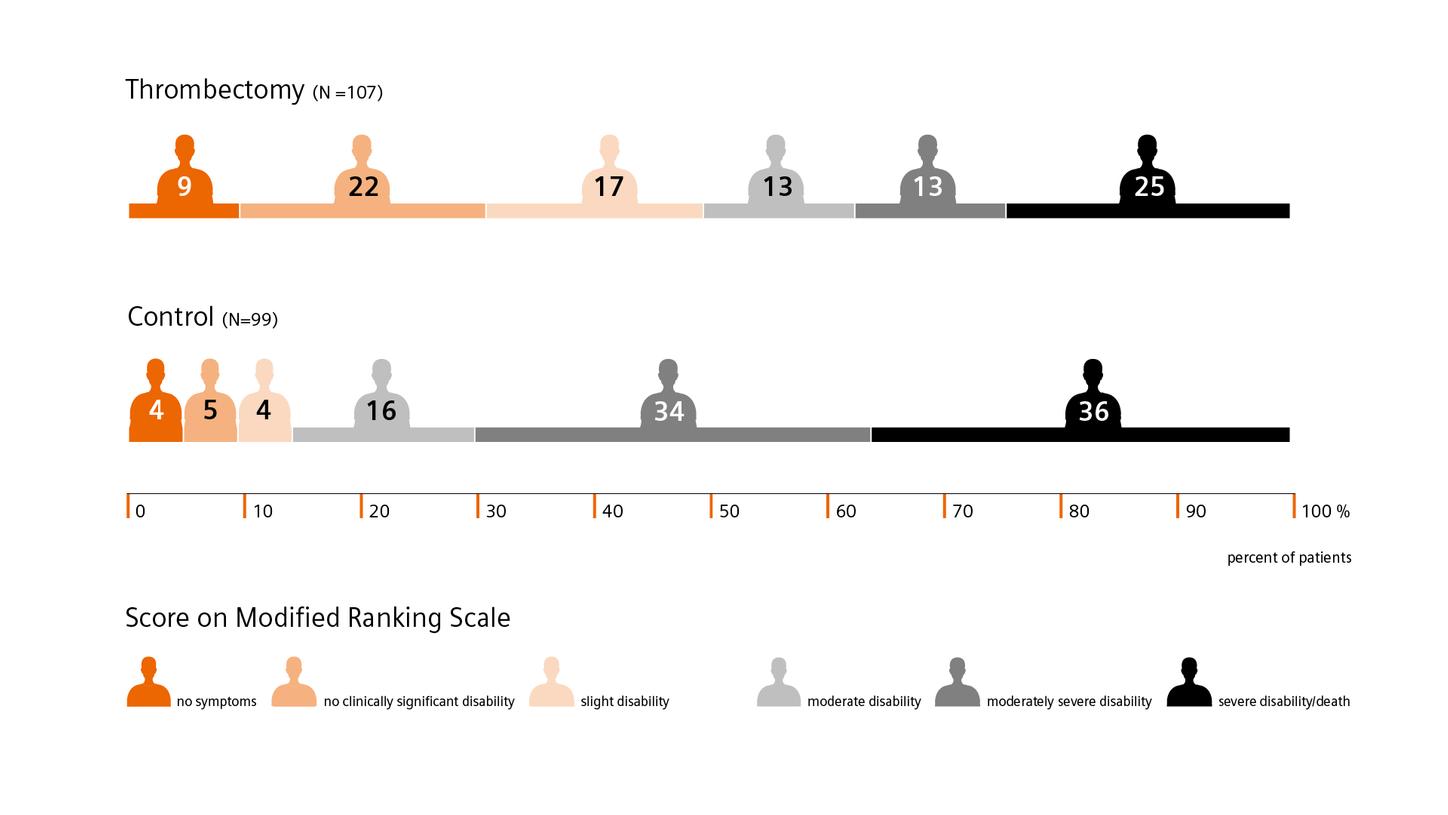

The DAWN trial shows that time alone shouldn’t be a disqualifier for endovascular thrombectomy. For example: 48.6% of patients in the thrombectomy group experienced less disability, compared to 13% in the control group who received standard medical care.4

The DAWN trial shows that time alone shouldn’t be a disqualifier for endovascular thrombectomy. For example: 48.6% of patients in the thrombectomy group experienced less disability, compared to 13% in the control group who received standard medical care.4